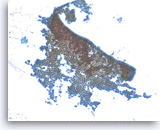

Benign pancreatic acini,

Pancreas FNA, Cell Block.

Normal pancreatic acinar cells are small and have granular cytoplasm, arranged in an acinar pattern.

40X